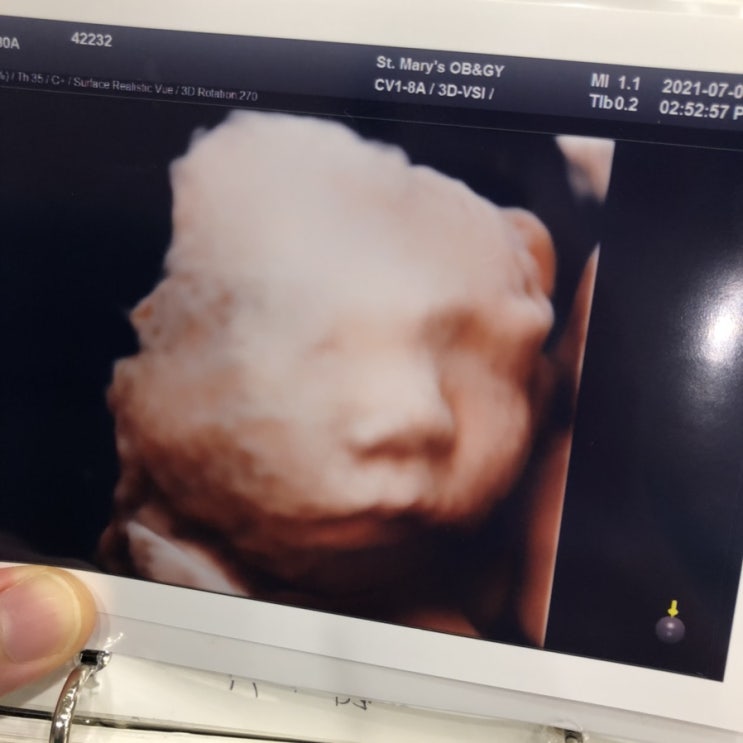

낳고 보니 입체 초음파촬영이랑 너무 똑같아서 신기 내눈에만 그렇게 보이나 ㅋㅋㅋ겸댕쓰 #부평성모산부인...

#임신중기 #임신후기 #입체초음파 #아기얼굴 #불면증 #역류성식도염 30주 3일을 지나고 있는 임신 후반부 ...